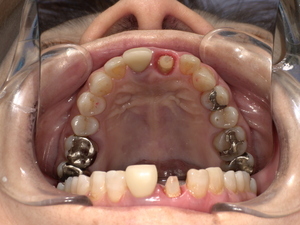

口腔内を詳しく診査した結果、

・前歯の被せ物が外れている

・歯の大部分が欠けている

・歯の土台が弱くなっている

という状態でした。

①支台築造(歯の土台作り)

歯の欠損が大きかったため、まず歯の土台を作りました。